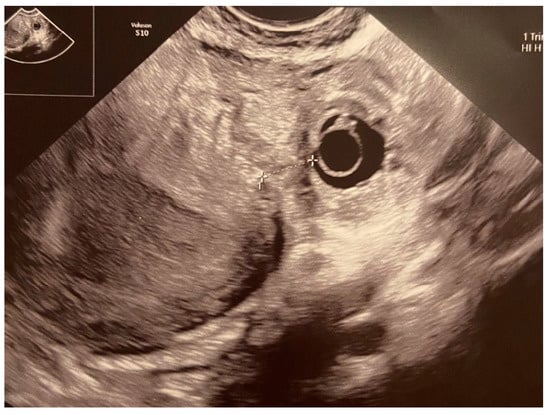

- An empty uterine cavity;

- A chorionic sac located eccentrically and at >1 cm from the lateral edge of the uterine cavity;

- A thin (<5 mm) myometrial layer surrounding the chorionic sac;

- The interstitial line sign;

- No double decidual sac sign, typically seen in the intrauterine pregnancy.